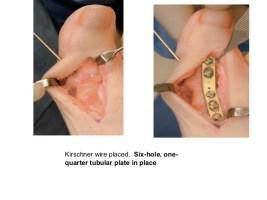

La cirugía está indicada cuando el dolor persiste. Si pasamos por el quirófano resolveremos el problema pero no se garantiza que no vuelva a ocurrir. Es decir, que en muchos casos este problema surge de nuevo con el tiempo.

Los remedios que se suelen adoptados para el tratamiento del hallux valgus se fabrican a partir de interventos quirúrgicos y del uso de métodos correctivos.

La cirugía de hallux valgus es lo único que ofrece resultados más fiables, aunque no siempre permanentes. El estudio realizado por el Dr. Nikolaus Wülker junto a su compañero de trabajo el Dr. Falk Mittag demuestra que en el caso de la intervención quirúrgica aproximadamente el 85% de los pacientes que fueron operados habían resuelto el problema y el 10% notó una mejora de la situación. También hay que decir que el 5% restante no tuvo ninguna mejora. Pero recordad que muchas veces vuelve a aparecer de nuevo con el tiempo.